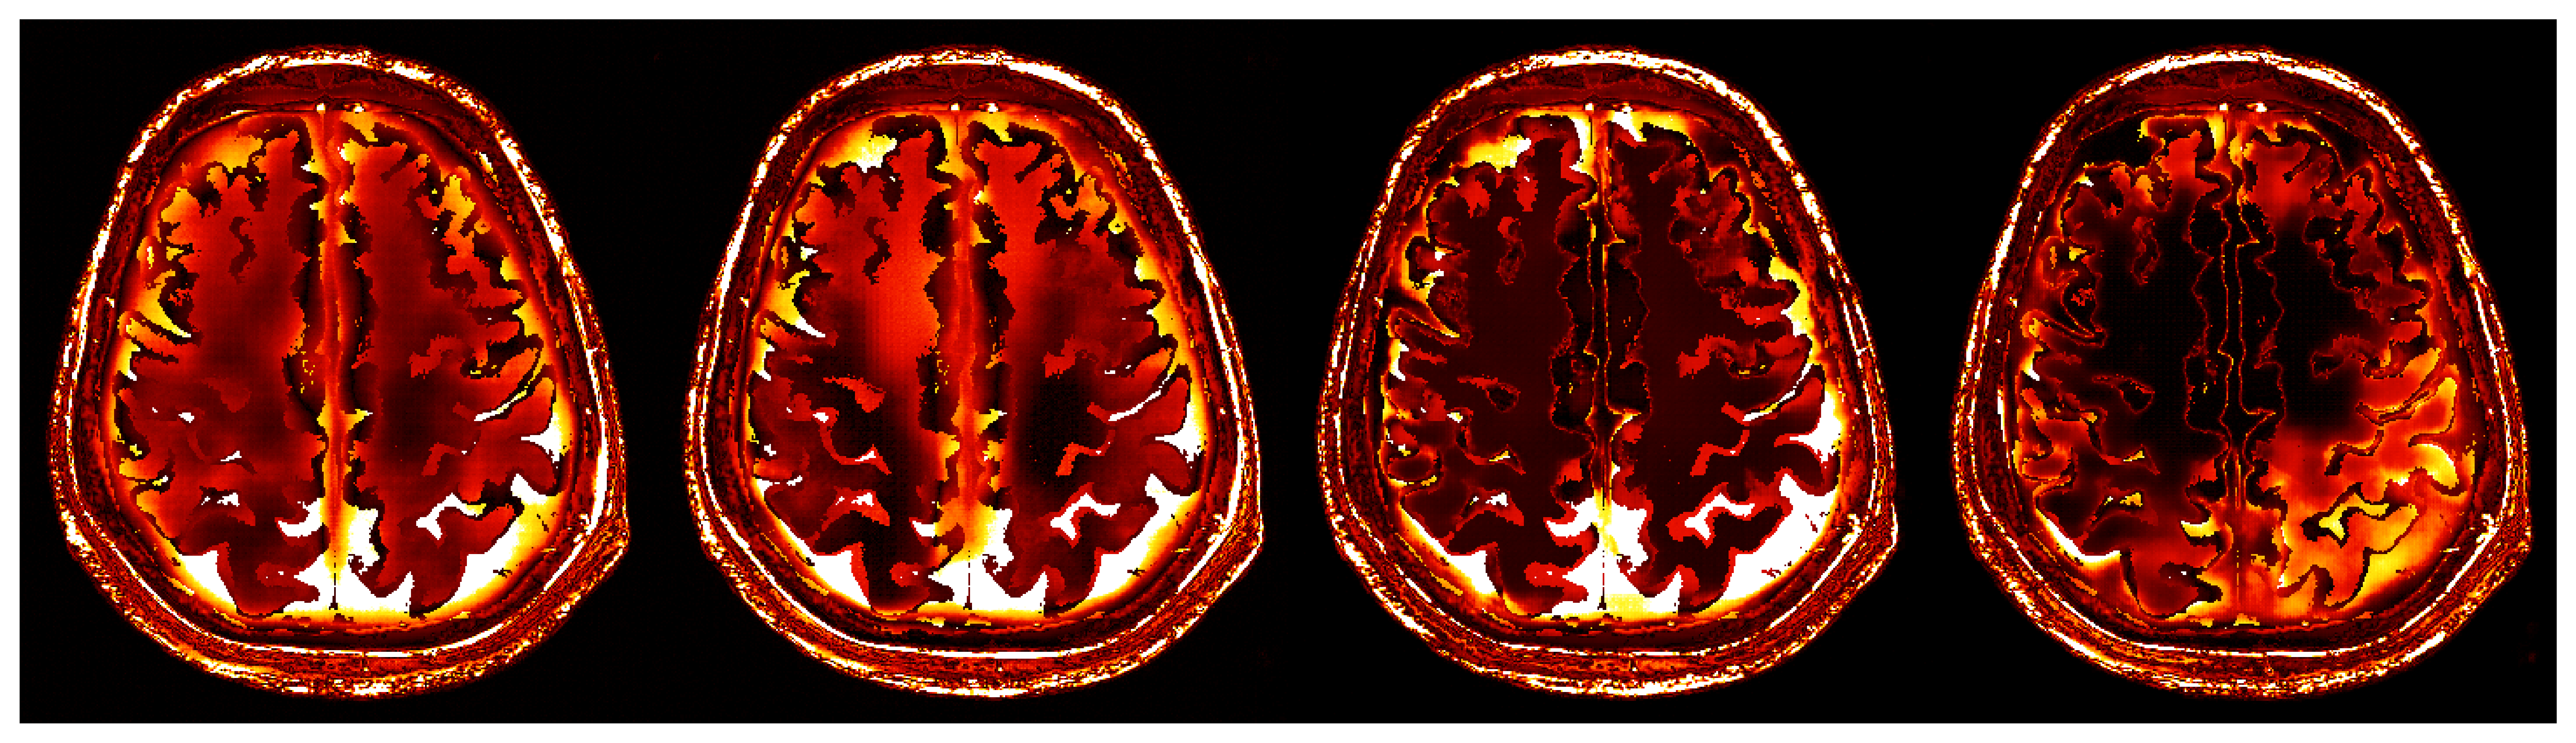

To overcome the end-to-end inference problem, we apply one iteration of ASPIRE by training a CNF on pairs, , where the ’s represent the score-based summary statistics at the fiducial points, , taken to be the uniform water velocity for all samples. An example of this initial summary statistic is shown in Figure 8. While the outer edge of the skull is reasonably well delineated, the inner edge of the skull is still poorly resolved and details inside the skull are mostly absent. However, the inference based on these initial summary statistics, shown in Figure 9, present a significant improvement over the baseline (cf. Figure 7), despite the presence of strong imaging artifacts in the summary statistics. The improvements concern the skull’s structure in particular, although details within the skull remain elusive due to the summary statistic’s limited information. To enhance fidelity further, ASPIRE 2 (shorthand for ASPIRE at iteration ) is applied by recalculating the score at the new posterior mean estimate for each training sample. Given these new training pairs, the next CNF is trained. While posterior sampling is efficient with CNFs (using Equation 4), recalculation of the score for each sample is computationally intensive, a topic we address in Section 6.6.

4.5 Amortized inference with iterative refinements

After the refinements of ASPIRE 2, significant improvements are evident in the posterior samples, particularly in capturing the structures within the brain tissue itself. The mean of these posterior samples, displayed in Figure 10, is clearly enhanced in resolution and details. We attribute these enhancements to the increased informativeness of the summary statistic in the second iteration compared to the information yielded by the initial iteration. A detailed inspection of the second summary statistic (shown in Figure 8) reveals more detail on the internal brain structures. Unlike the first summary statistic (cf. Figure 8), which primarily delineated the skull, the second iteration’s summary statistic better ‘illuminates’ the softer tissues within the brain, offering a more informative image for the posterior network. Thanks to accounting for the scattering at the skull, the acoustic illumination of the brain is improved significantly. Accurately resolving the skull structure is an important consideration as noted by [65].

As one can observe from Figure 10, the reconstruction quality improves for increasing number of refinements of ASPIRE. By virtue of the iterative recalculation of the score-based summary statistic, the method is progressively able to discern finer details within the brain albeit the updates become less pronounced as the number of refinements increases. We further illustrate this refinement by plotting posterior samples from all four ASPIRE iterations in Figure 21. Practically, a user of ASPIRE can decide on the number of refinements based on the amount of compute available or by refining until there are diminished returns on enhancements.